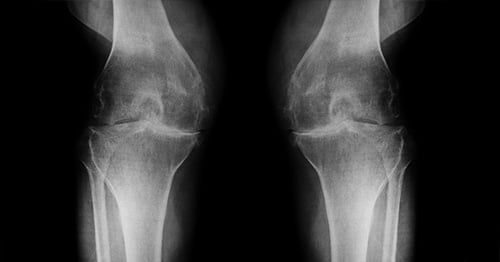

- MRI (magnetic resonance imaging): This can reveal subtle, early changes in bony and soft tissues of the joint.

MRI of the knee showing normal cartilage on one side and cartilage loss and an osteophyte on the other.